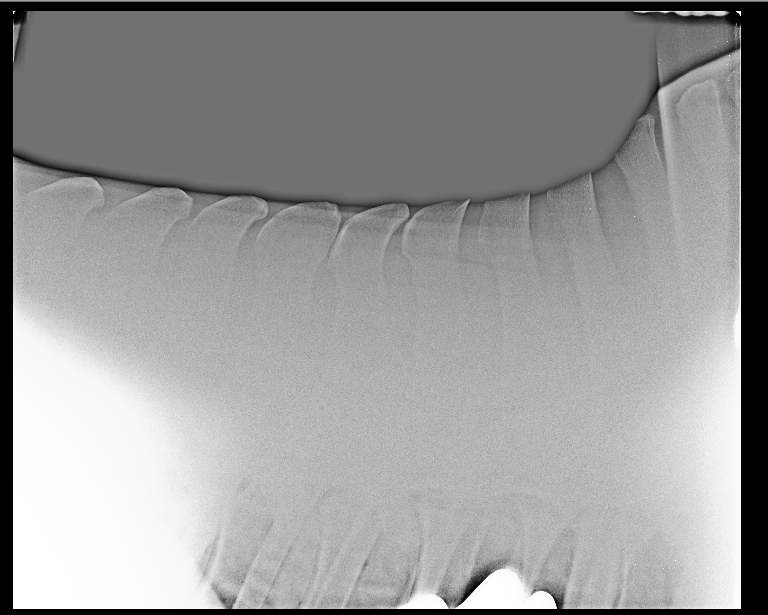

En het gevoel werd bevestigd, Diva heeft Kissing Spines en slijtage in haar hoefbeen.

Onder verdoving zijn de plekken in haar rug en voorbenen(hoeven) ingespoten.

Onder nog 2 foto's van de KS, en een foto in training van gisteren.